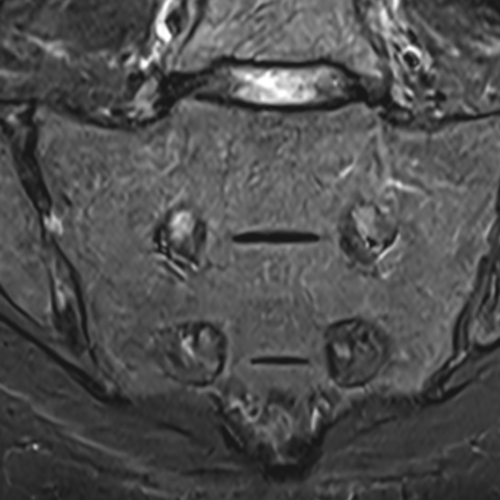

Cet examen est réalisé pour analyser les articulations sacro-iliaques en cas de douleurs, lombalgies ou fessalgies (pygalgies).

Quels sont les résultats possibles d’une IRM des sacro-iliaques ?

Cette examen permets de diagnostiquer:

- les sacro-iliites (inflammation de l’articulation) notamment dans la Spondylarthrite ankylosante ( SPA ) avec :

œdème osseux (inflammation active)

érosions de l’os

synovite (inflammation de la membrane articulaire)

épanchement articulaire

- les atteintes chroniques (lésions anciennes) de sacro-iliites :

sclérose osseuse

ponts osseux

ankylose (fusion de l’articulation)

- les arthrose sacro-iliaques :

pincement de l’espace articulaire

ostéophytes (petites excroissances osseuses)

sclérose de l’os

- les sacro-iliite infectieuses :

inflammation importante

abcès possible

atteinte des tissus autour

- l’ostéose condensante : Il s’agit d’une condensation de l’os (sclérose) au niveau de la partie iliaque de l’articulation sacro-iliaque